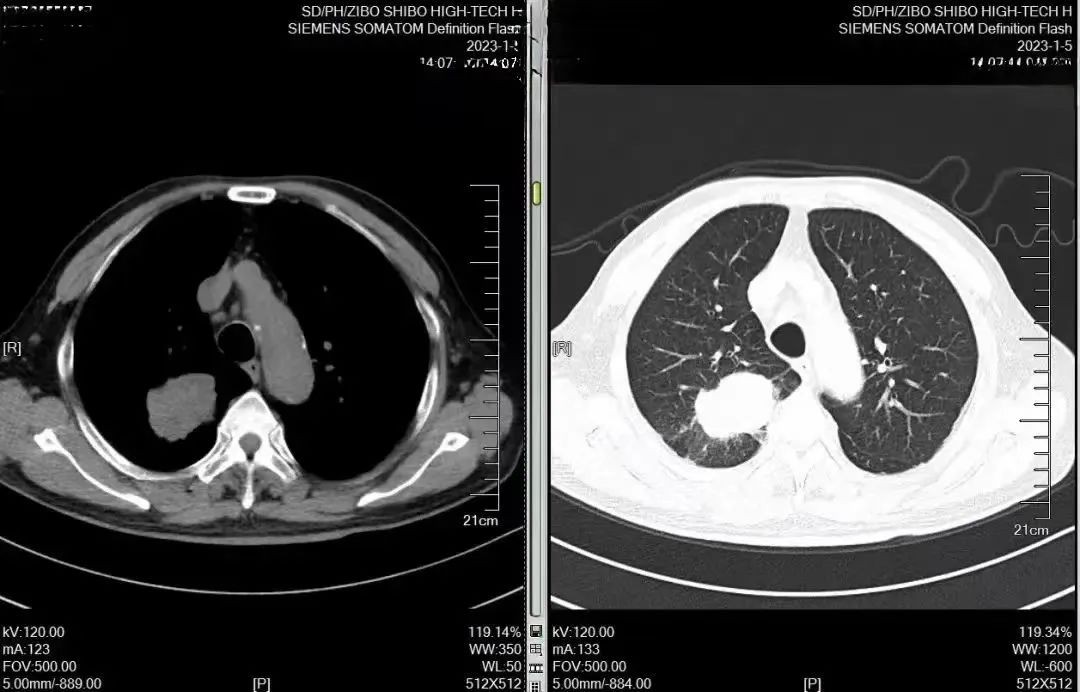

一份努力,一分收获,作为世博高新医院的医护人员,患者对服务和医术的满意和认可就是最大的收获。近期,世博高新医院胸外科收到了一份来自

2024-01-29